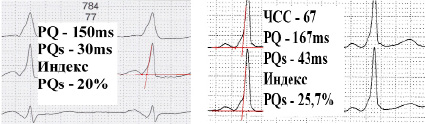

Укороченный интервал pq у взрослых что это. Синдром укороченного pq на экг. укорочение интервала pq на экг. феномен укорочения интервала pq. феномен укороченного pq.